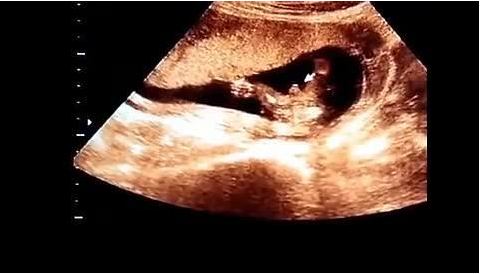

健康咨询描述:怀孕四个月B超图胎儿应该是什么姿势的 你好,胎儿四个月的姿势是不固定的,因为胎儿还小,

这个时候,准妈妈已经度过了最危险的孕早期,而这时的胎儿长什么样了呢?一起来看看“怀孕四个月胎儿图”。

此时的妈妈们肯定都很想看关于怀孕怀孕四个月按孕周期计算的话,即是怀孕13周-16周,孕妇此时做彩超可以

那么,怀孕四个月的男胎儿图究竟是怎样的呢?怀孕第4个月时,母亲的腹部微微突起,但还不是很明显。